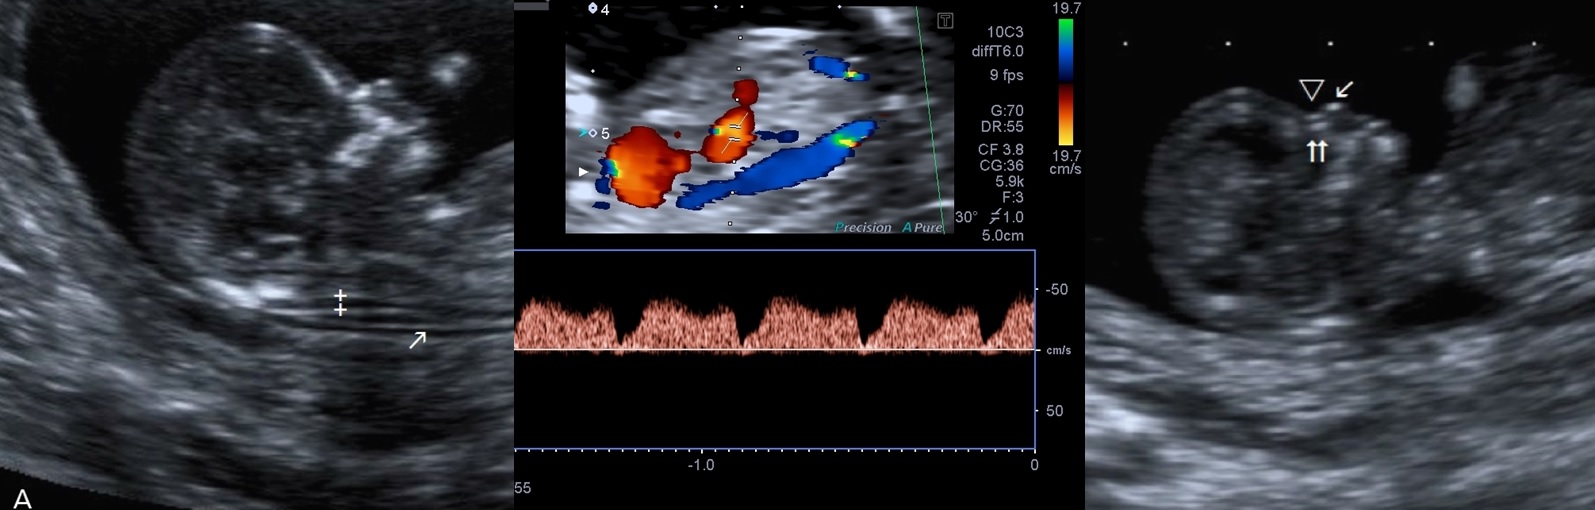

Duktus venozus

Göbek kordonundan temiz kan getiren damarın, kalbin sağ kulakçığına gelmeden önce bebek karaciğeri içinden geçen bölümünün renkli doppler kullanılarak incelenmesi.

İncelemenin çok önemli bir kısmı siyah-beyaz (2D). Bu incelemede kullandığımız tek ‘renkli’ kavramı damarlardaki kan akımını incelediğimiz ‘renkli doppler’ dir. Fakat halk arasında ‘renkli ultrasonografi’ tanımı, 3 veya 4 boyutlu (3D/4D) ultrasonografik inceleme yerine kullanılmaktadır. Kullandığımız cihaz 3D/4D özelliği olan gelişmiş bir cihazdır. Bu nedenle bizim için önemli olan 2D kesit kalitesi üst düzeydedir ve yaptığımız incelemeyi kolaylaştırır.